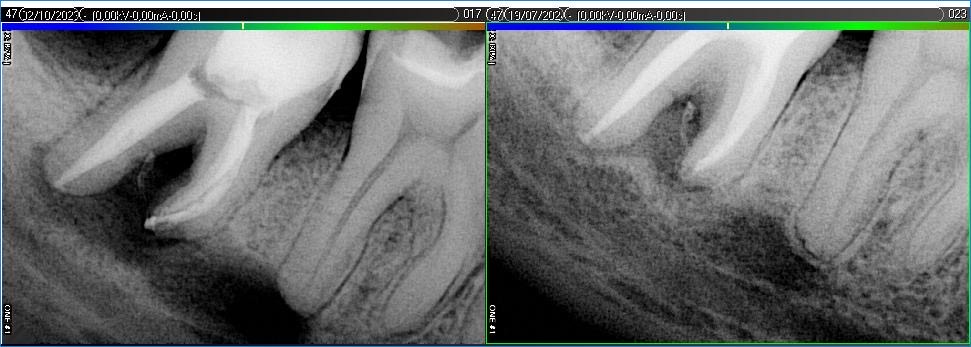

Вилучення інструменту з каналів зуба